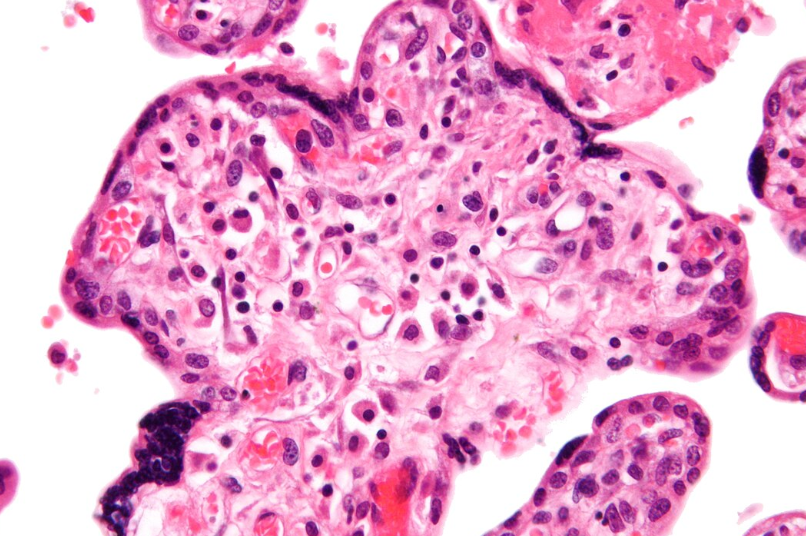

Noma, özellikle çocuklarda görülen ve ağız ile yüz bölgesinde hızlı ilerleyen ölümcül bir enfeksiyon hastalığıdır. Noma, tıbbi adıyla Cancrum oris veya gangrenöz stomatit olarak bilinir ve genellikle 1 ila 16 yaş arasındaki çocuklarda, özellikle de 1-4 yaş aralığında en yüksek sıklıkla ortaya çıkar. Hastalık, ağız içindeki mukozada küçük bir ülser şeklinde başlar; ancak kısa sürede diş etleri, yanak, dudak, dil, çene kemiği ve hatta burun gibi çevre dokulara yayılır. Bu süreçte yumuşak dokular ve kemikler hızla nekroza uğrayarak erir, yüzün yapısını bozar ve kişinin hem fiziksel görünümünü hem de yaşam fonksiyonlarını ciddi şekilde etkiler. Noma’nın en önemli nedenleri arasında yetersiz beslenme, bağışıklık sisteminin zayıflığı, kötü ağız hijyeni ve enfeksiyonlara açık yaşam koşulları bulunur. Hastalık özellikle Sahra altı Afrika’daki yoksul bölgelerde yaygındır ve burada 1000 çocukta 1 ila 7 vaka görüldüğü tahmin edilmektedir. Tedavi edilmediğinde ölüm oranı son derece yüksektir; çünkü enfeksiyon hızla ilerleyerek kan dolaşımına karışabilir ve sistemik komplikasyonlara yol açabilir.

Noma, ağız içinde küçük bir yara veya ülserle başlar. Kısa sürede bu yara diş etlerine, yanaklara, dudaklara ve çene kemiğine yayılır. Hastalık ilerledikçe:

• Yüzde deformasyon ve doku kaybı gibi belirtiler ortaya çıkar. Bu süreç çok hızlı ilerler; birkaç gün içinde yüzün büyük bir kısmı nekroza uğrayabilir.